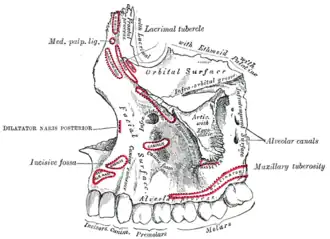

Mouth (oral cavity) Left maxilla. Outer surface.